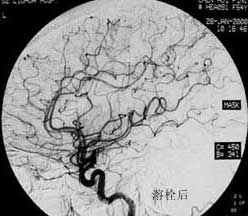

血管内栓塞对于单支或少数供血动脉的AVM,特别是新近出血的病例,可以达到微侵袭、痛苦小、疗效迅速的目的。

近来改变栓塞方式,将导管直接放置 畸形血管团内,注射NBCA胶,可使畸形团的解剖 治愈率提高至27%。再加上更细、超滑的微导管问世,栓塞的并发症更为降低。针对大型、功能区 的AVM栓 塞可缩小其体积,改善血液动力学分布,以利于显微外科技术切除或放射外科治疗,是后二者的重要辅助手段。